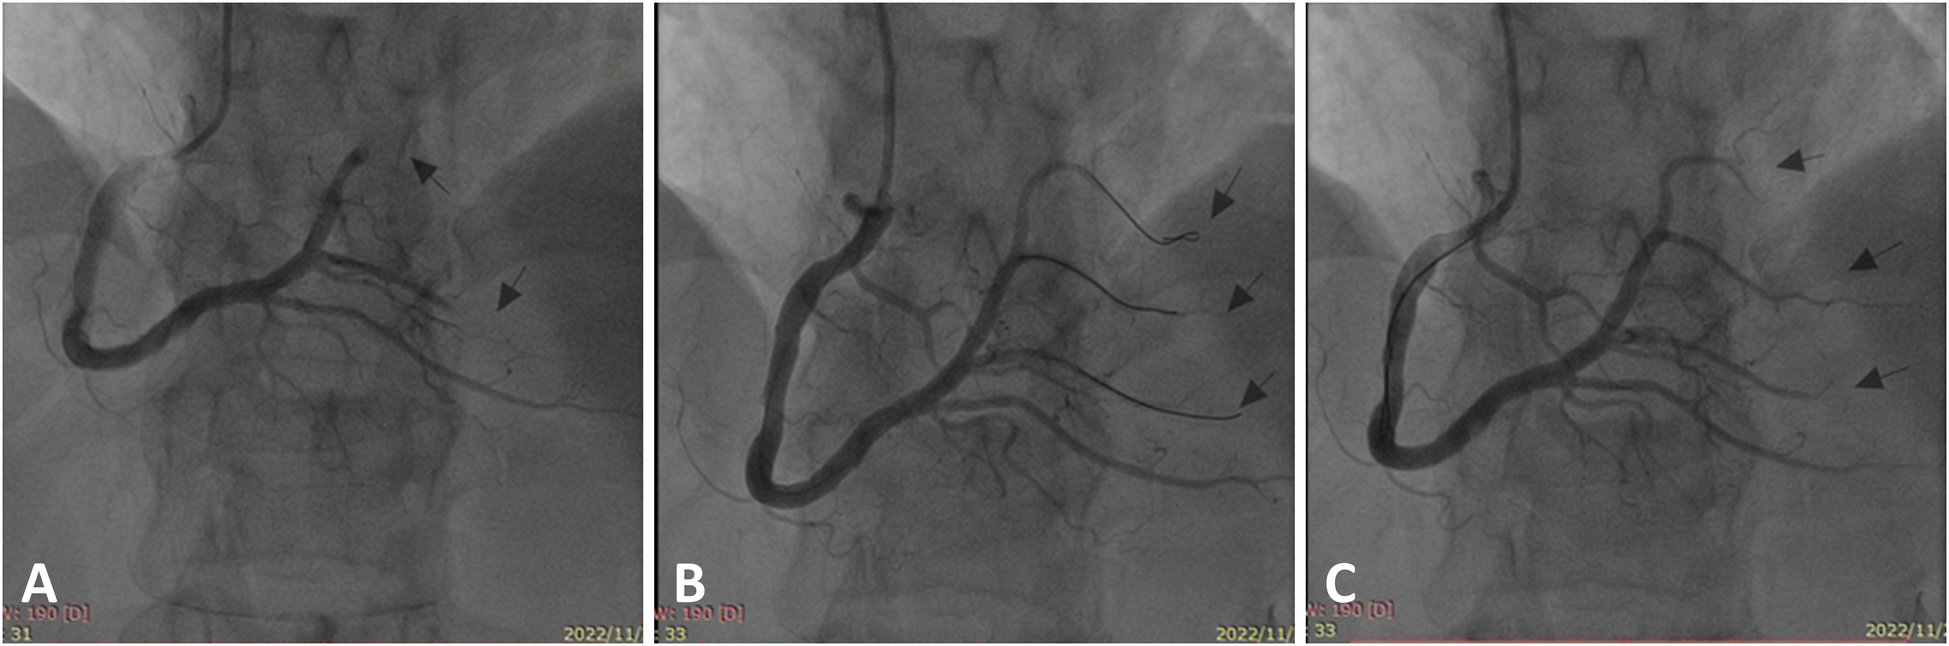

Emergency coronary angiography was performed, revealing a right-dominant coronary artery system with normal openings of the left and right coronary arteries. The left main stem displayed no significant stenosis. The left anterior descending and circumflex branches featured normal openings and courses without obvious stenosis. The right coronary artery was enlarged with a normal opening and course. The posterior left ventricular branch (PLB) of the right coronary artery exhibited distal occlusion, and the first branch of the PLB displayed distal occlusion with visible thrombus (Figure 1A). Considering the patient's history of AA and significant thrombotic burden, we decided to perform coronary angioplasty without stent placement. The guidewire smoothly passed through the occluded segment (Figure 1B). Using a compliant balloon, the stenotic segment was dilated. The thrombus was aspirated. Thrombolysis in Myocardial Infarction (TIMI) 3 flow was achieved in all branches of the right coronary artery and PLB, with no significant local stenosis observed (Figure 1C). The ST segment in leads II, III, and aVF significantly decreased on cardiac monitoring. The patient's chest pain disappeared.

Figure 1

Right coronary artery under the initial coronary angiography. (A) Occlusion of the distal posterior left ventricular branch and its first branch (arrows). (B) The occluded site was opened by a guidewire (arrows). (C) After balloon dilation and thrombosis aspiration, the final angiography revealed smooth blood flow in the distal branches of the right coronary artery with no significant stenosis (arrows).